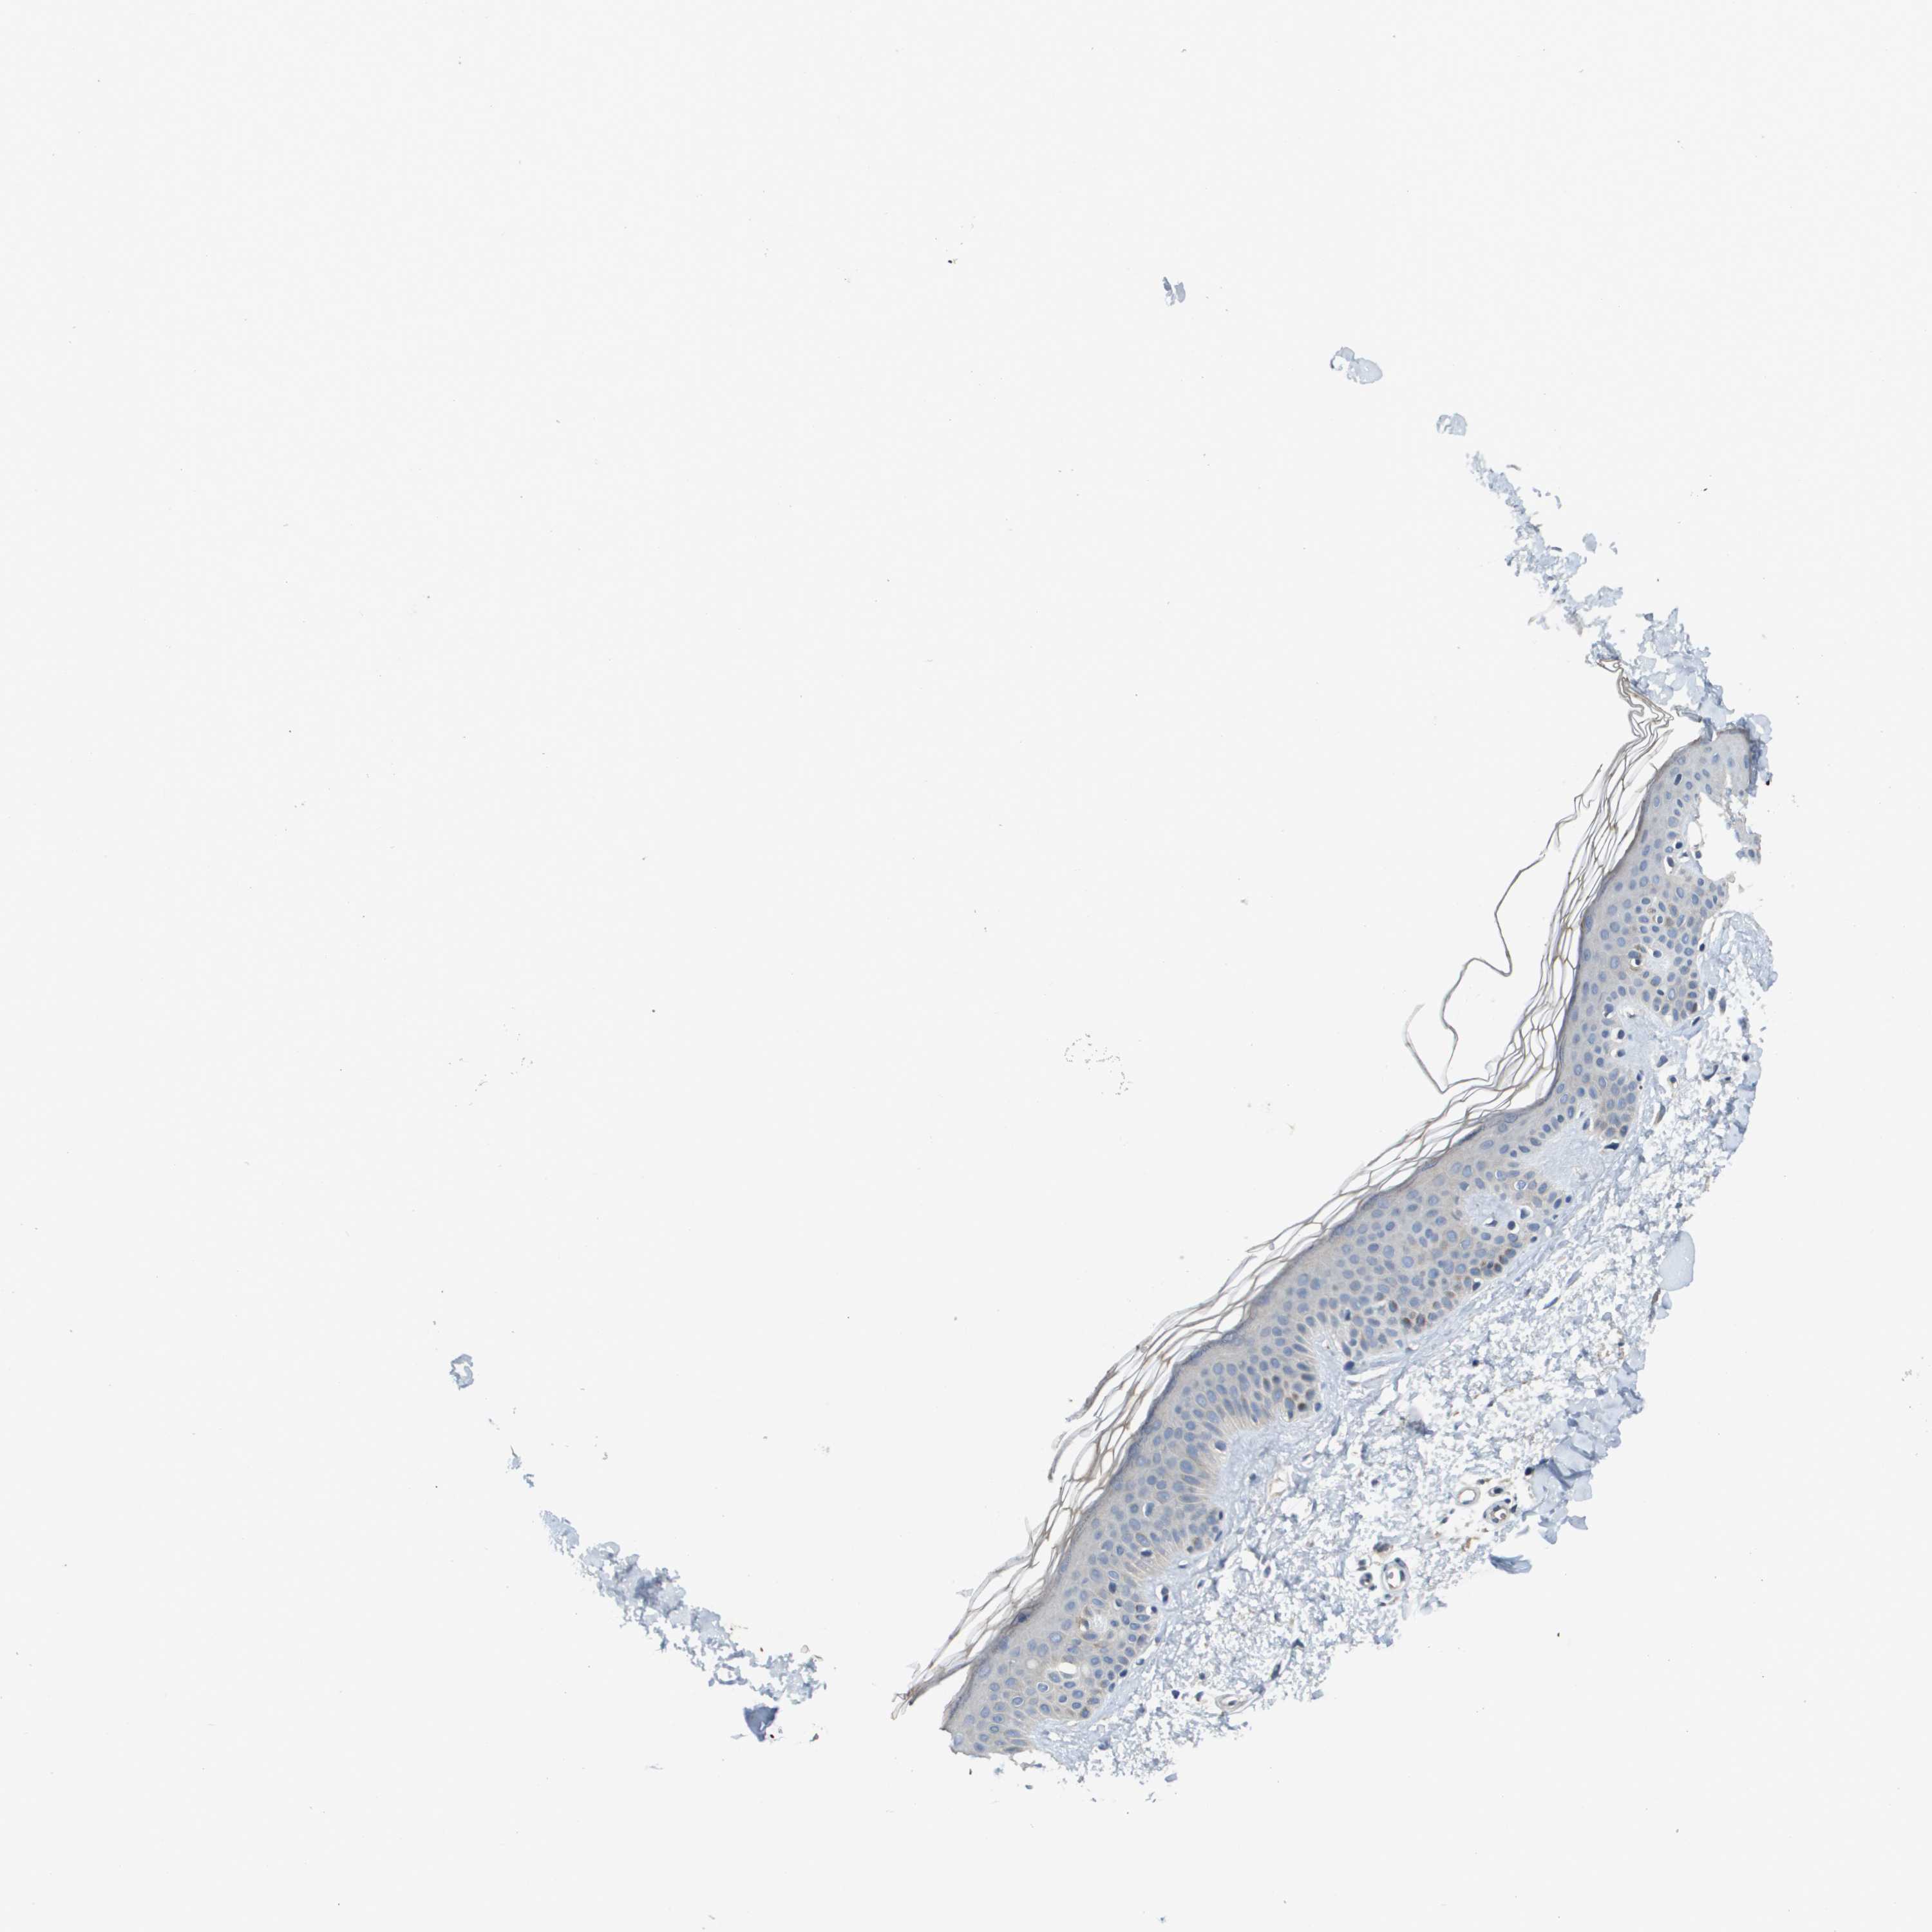

SKIN 2 - Antibody stainingi

Antibody staining in the annotated cell types in the current human tissue is reported as not detected, low, medium, or high, based on conventional immunohistochemistry profiling in selected tissues. This score is based on the combination of the staining intensity and fraction of stained cells.

Each image is clickable and will lead to virtual microscopy that enables deeper exploration of all samples and also displays staining intensity scores, fraction scores and subcellular localization as well as patient and tissue information for each sample.

Antibody HPA030955Antibody CAB018070

Epidermal cells LowNot detected